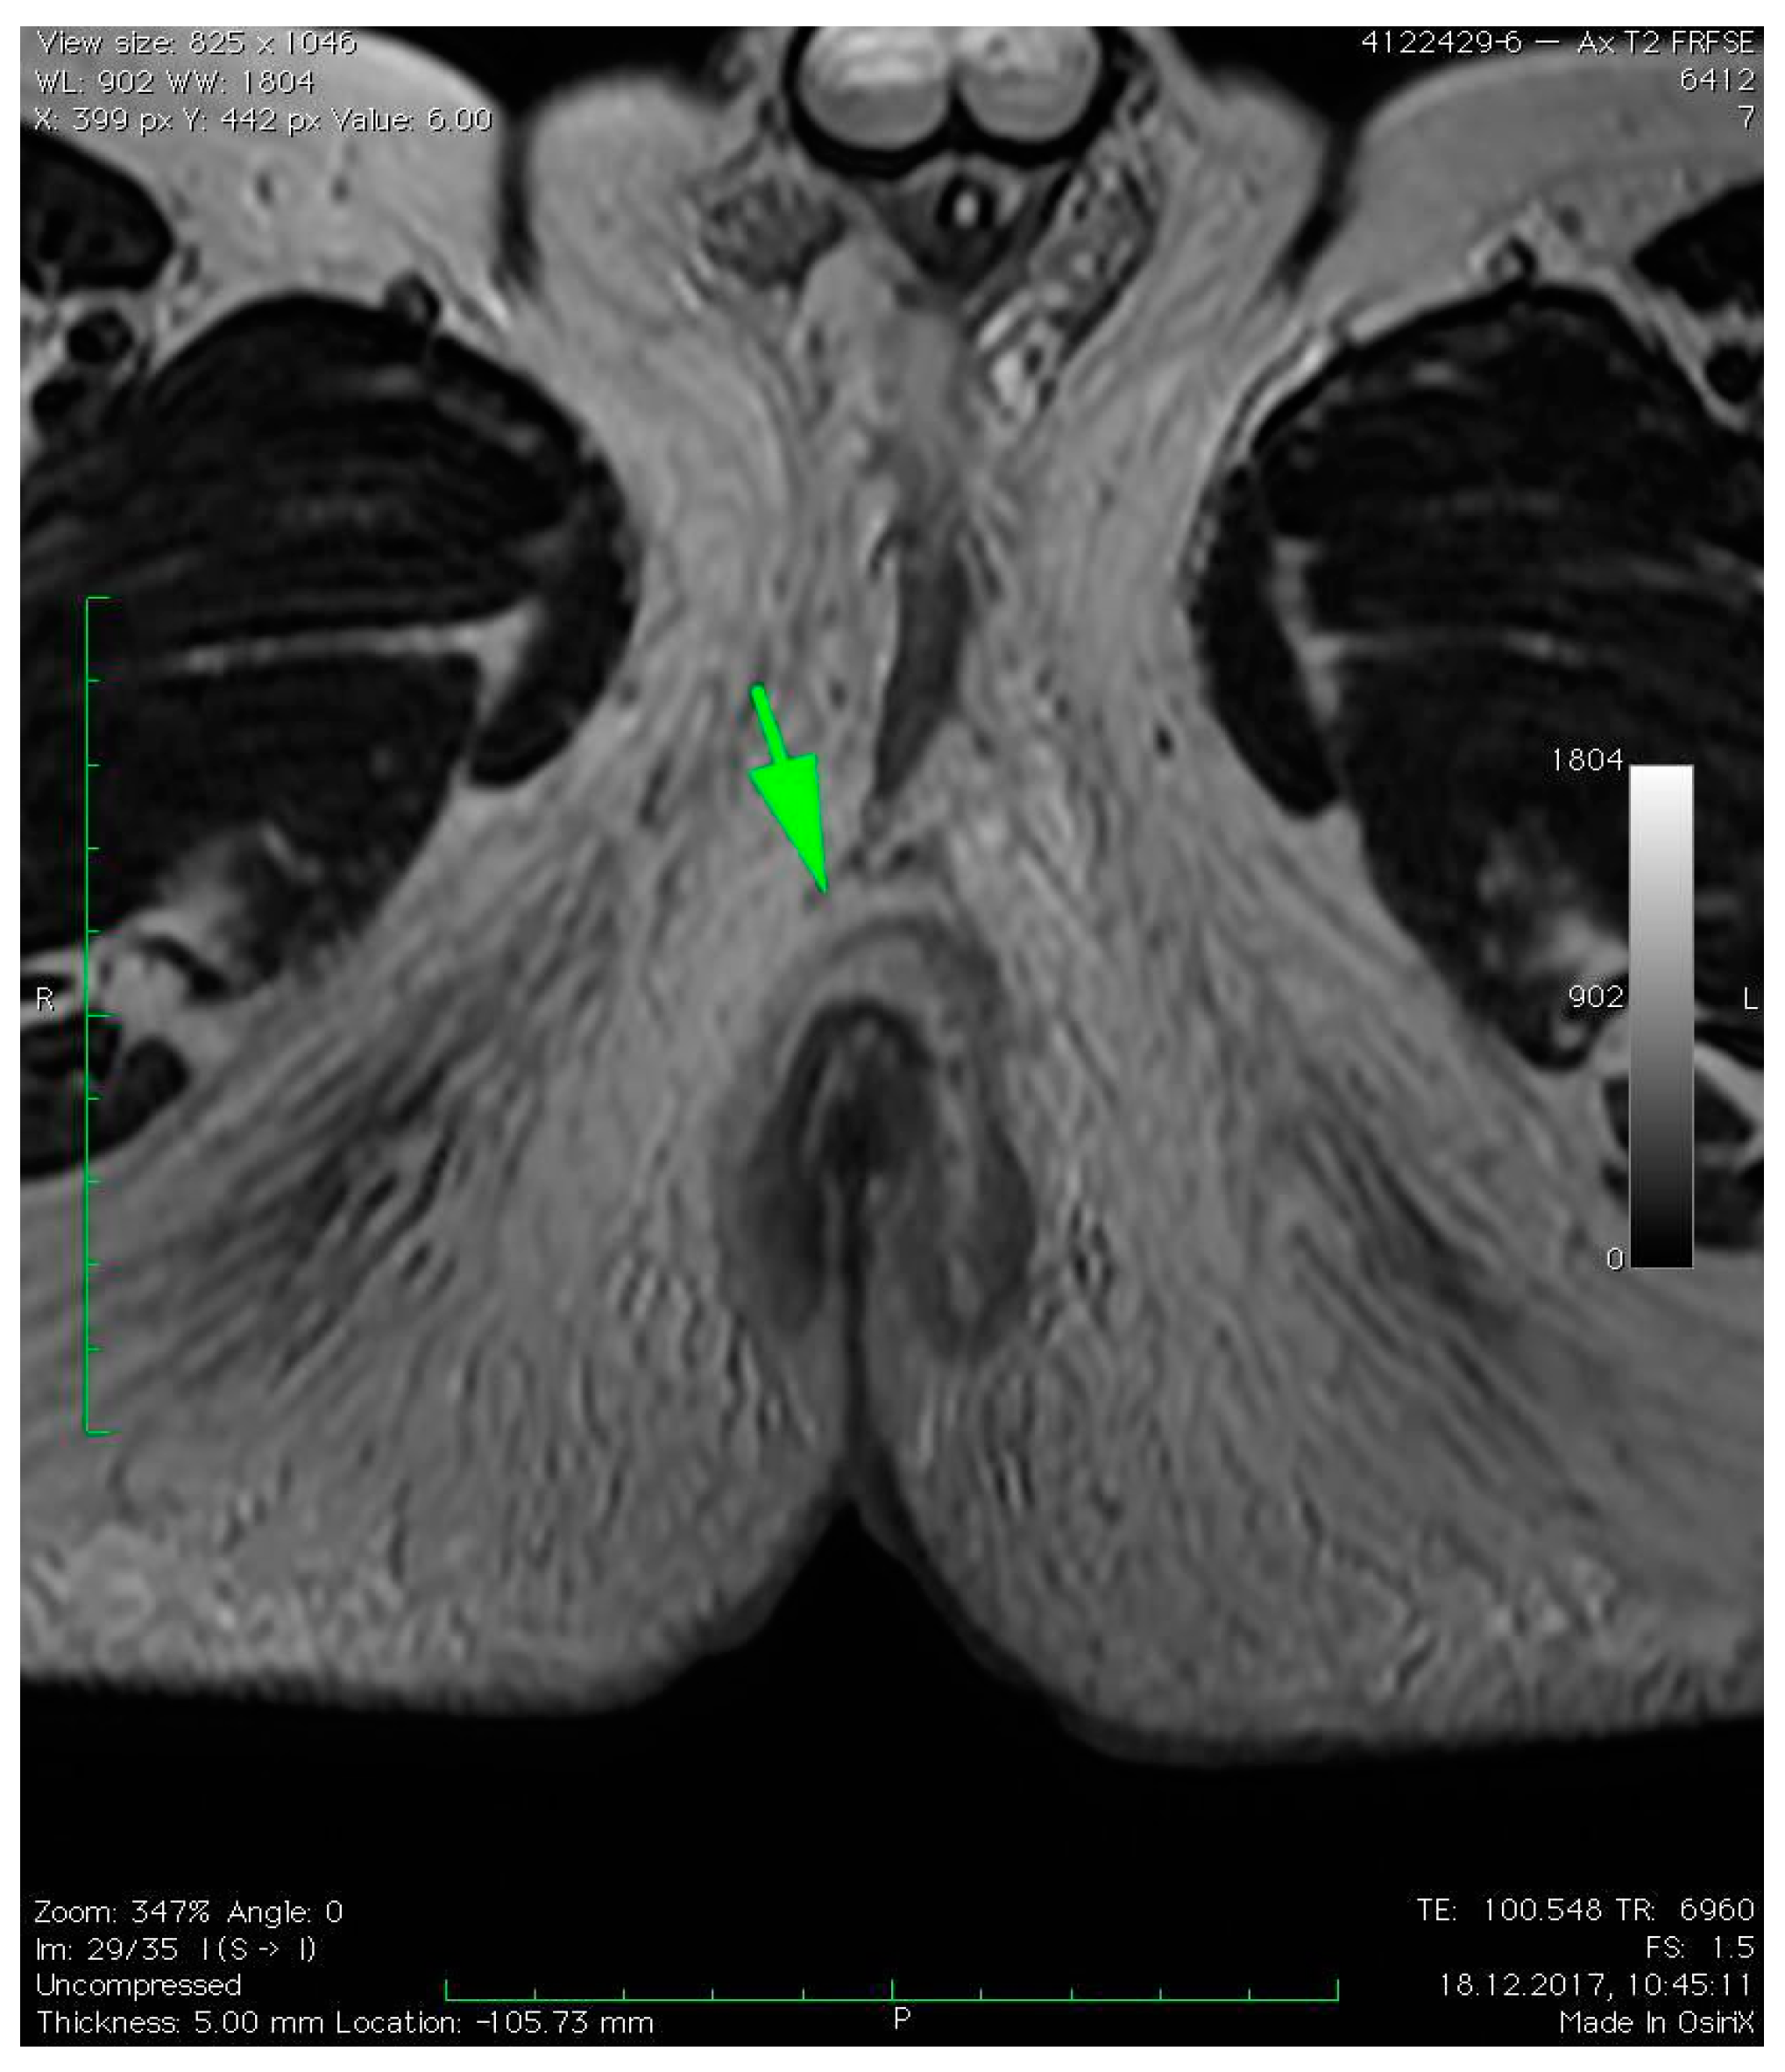

3. Case Presentation